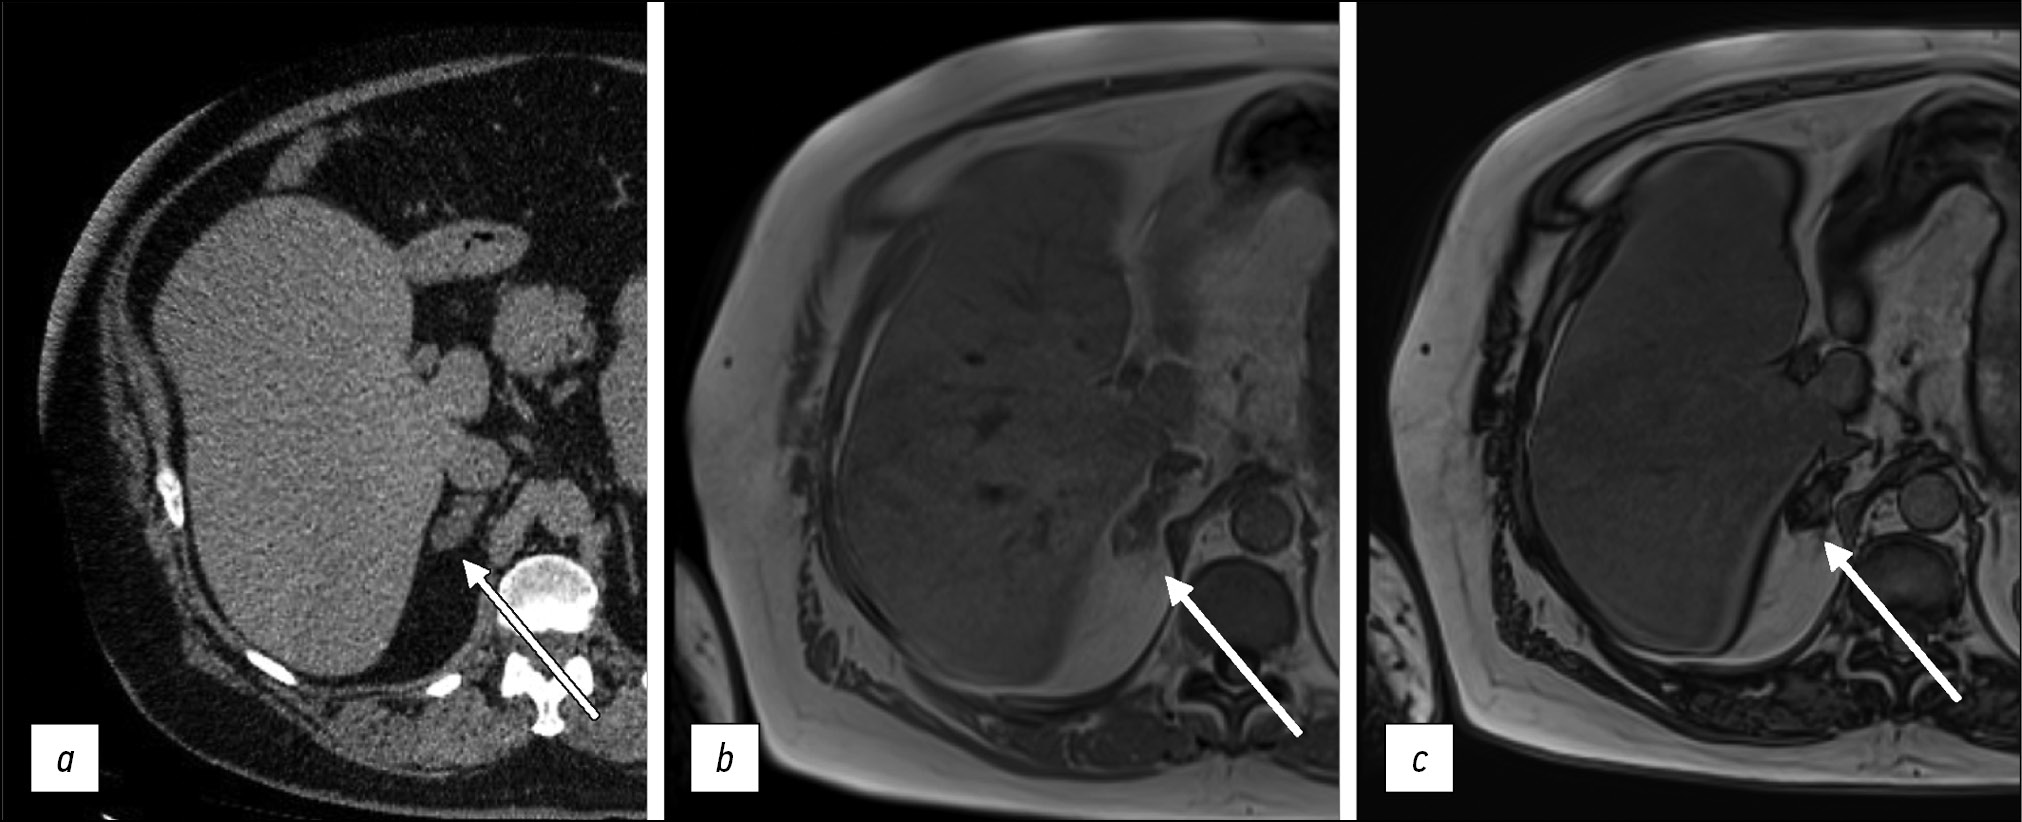

Another important aspect of T1-WIs is the use of intravenous contrast enhancement, including hepatospecific contrast agents. For example, gadoxetic acid has a high affinity for hepatocytes and thus allows for better visualization of liver pathologies (Fig. 1).

Figure 1. Liver magnetic resonance imaging with a hepatospecific contrast agent. A hepatocellular carcinoma nodule (arrows): a T2-weighted image: a hyperintense nodule is visualized; b Т1-weighted image, arterial phase: a ring-like contrast uptake is visualized; c Т1-weighted image, hepatospecific phase, 20 min after contrast agent injection.

Contrast agents shorten the T1 relaxation time, resulting in higher signal intensity on T1-WIs. Depending on the blood supply to focal or diffuse lesions in parenchymal organs, various contrasting patterns are distinguished, which in general differ from those in adjacent unaffected tissues. Arterial phase imaging is accomplished by short sequences immediately after the administration of gadolinium-based contrast agents.

The main method involves dynamic multiphase 2D or 3D SGE sequences, which can be used to analyze signal intensity–time curves in areas of interest. Most focal lesions (e.g., those in the spleen, liver, or pancreas) are best visualized during the arterial phase. Images taken 1.5–10 min after contrast agent injection are in the equilibrium contrast phase, with an optimal window of 2–5 min after injection. As a rule, 5 min after contrast agent injection, a delayed or excretory phase begins. Many inflammatory or neoplastic diseases are better visualized during this phase, and the addition of fat suppression aids in the detection of these changes (e.g., peritoneal implants, cholangiocarcinoma, inflammatory bowel disease, and adrenal masses) [7–9].